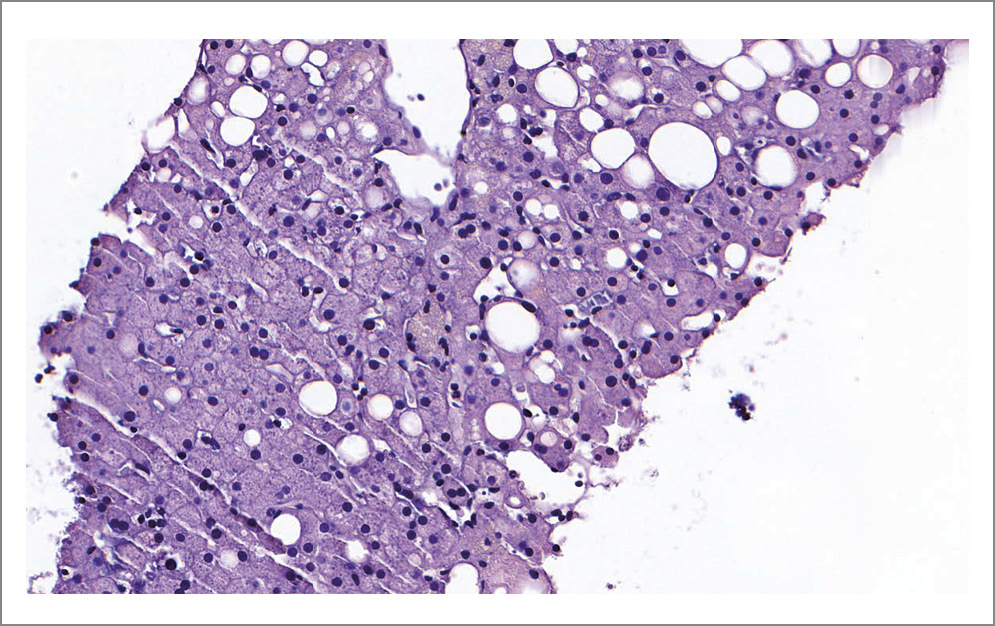

В мае 2022 г. проходила стационарное лечение в ГБУЗ «ГКБ им. С.П. Боткина» в отделении эндокринологии по поводу гипергликемии до 12 ммоль/л. В ходе дообследования выявлено повышение уровня γ-глутамилтрансферазы – до 46 ЕД/л, аспартатаминотрансферазы (АСТ) – до 37 ЕД/л, АЛТ – 64 ЕД/л, по данным УЗИ органов брюшной полости – гепатомегалия, субъективные признаки жирового гепатоза. Последняя госпитализация в гастроэнтерологическое отделение ГБУЗ «ГКБ им. С.П. Боткина» – в мае–июне 2022 г., отмечалась дислипидемия IIб [общий холестерин 7,06 ммоль/л, липопротеины низкой плотности (ЛПНП) – 4,84 ммоль/л, триглицериды – 2,34 ммоль/л], корректирована приемом статинов, выполнена биопсия печени (рис. 1, 2): хронический перипортальный и лобулярный гепатит, средняя активность. METAVIR A2F0. Индекс стеатоза 1.

Рис. 1. Окраска гематоксилином и эозином. Дольково-трабекулярное строение печени сохранено. Центральные вены не расширены.

Рис. 2. Окраска гематоксилином и эозином. Портальные тракты не расширены, с мелкоочаговыми лимфоплазмоцитарными инфильтратами, выходящие за пределы пограничной пластинки с единичными сегментоядерными нейтрофилами. Гепатоциты разнокалиберные с преобладанием средних размеров, встречаются крупные с картиной белковой дистрофии и наличием телец Каунсильмена. Очаговая крупнокапельная жировая дистрофия гепатоцитов (не более 15% клеток). Гиперплазия клеток ретикулоэндотелиальной системы.